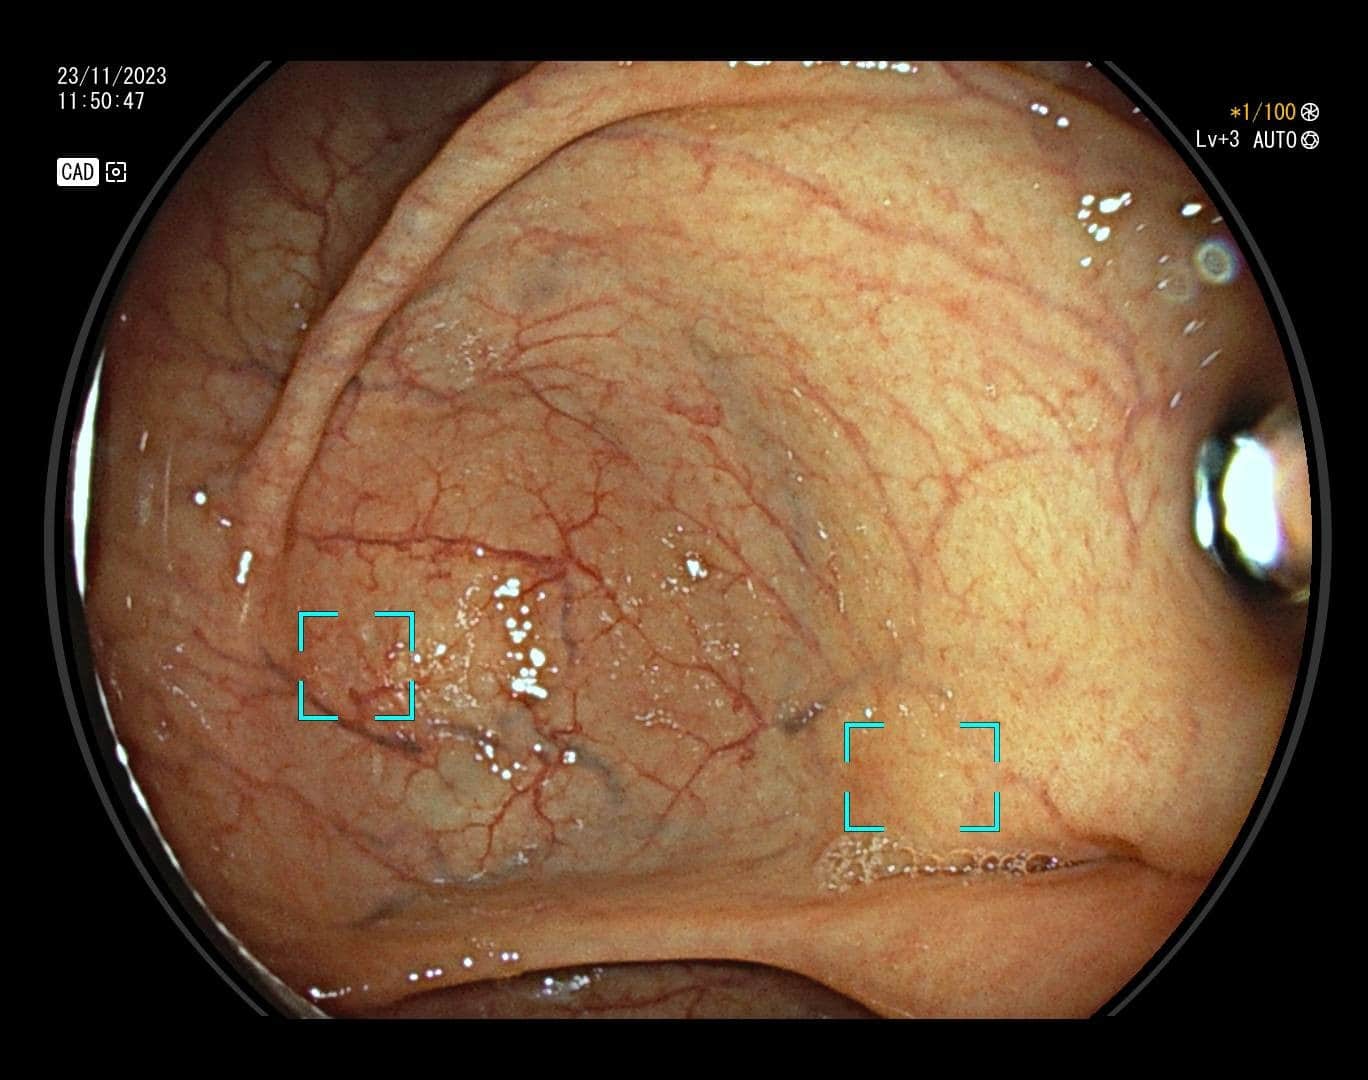

Karcinom debelog crijeva, prema podacima Hrvatskog registra za rak, drugi je po učestalosti uzrok maligne bolesti u žena, a treći u muškaraca. Ova vrsta raka razvija se iz polipa, malih izraslina na sluznici debelog crijeva koje nastaju pod utjecajem okolišnih i/ili genetskih čimbenika. S vremenom polip raste, stanice nakupljaju mutacije, te u konačnici dolazi do razvoja karcinoma. Na sreću, nemaju svi polipi zloćudni potencijal. Kod polipa visokog rizika proces do maligne transformacije je najčešće dugotrajan što nam daje priliku za preventivnim djelovanjem – preventivnu kolonoskopiju preporučuje se učiniti s navršenih 50 godina života, a u slučaju obiteljske sklonosti i u ranijoj životnoj dobi. Cilj pretrage nije dijagnosticirati karcinom već pravovremeno detektirati i ukloniti njegov predstadij – polip.

Kako bi pregled debelog crijeva bio temeljit potrebna je dobra priprema crijeva (očišćenost), no mali i plitki polipi, unatoč optimalnim uvjetima pretrage mogu ostati nezamijećeni, a zbog anatomije crijeva i skriveni iza nabora.